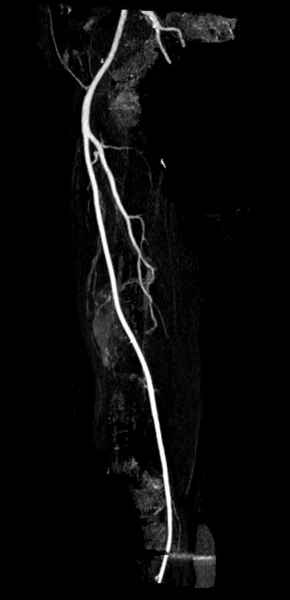

В зависимости от характера опухоли некоторые патологические переломы имеют риск кровотечения во время операции. Множественные литературные данные подтверждают, что надо проявить осторожность при интрамедуллярном остеосинтезе при неизвестных опухолях, особенно где имеется подозрение на Renal Cell Carcinoma. (RCC- hypernephroma) http://www.bonetumor.org/tumors/pages/page64.html

Для предупреждения кровотечения во время рассверливания, за день до операции провели эмболизацию сосудов питающий метастаз. http://radiology.rsnajnls.org/cgi/reprint/150/3/673.pdf (7-11, 12-15-16)